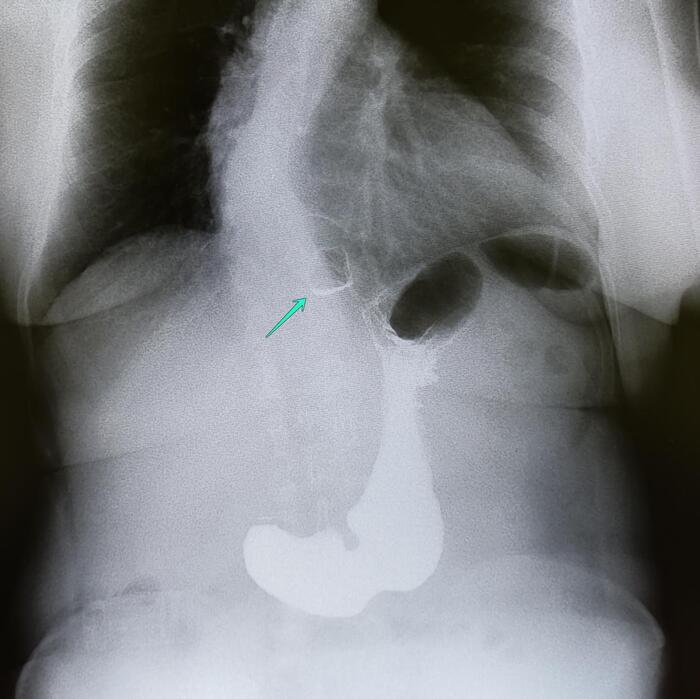

Эностоз-компактный островок остеосклероза

Эностоз, или костный островок, представляет собой доброкачественное образование в костной ткани, которое обычно обнаруживается случайно при рентгенологическом исследовании.

-Компактный костный островок(эностоз) дистальной фаланги пятого пальца правой кисти.

Основные рентгенологические признаки эностоза включают:

Очаговое затемнение:

На рентгенограмме эностоз выглядит как четко очерченный очаг повышенной плотности (гиперденсивный) в костной ткани.

Форма и контуры:

Образование обычно имеет округлую или овальную форму.

Контуры четкие, ровные, иногда могут быть слегка лучистыми или неровными, но без признаков агрессивного роста.

Локализация:

Эностоз может встречаться в любой кости, но чаще всего обнаруживается в губчатом веществе костей (например, в позвонках, тазовых костях, ребрах, длинных трубчатых костях).

Размер:

Размеры эностоза обычно небольшие (от нескольких миллиметров до 1-2 см), но могут варьироваться.

Отсутствие деструкции окружающих тканей:

Эностоз не вызывает разрушения окружающей костной ткани и не сопровождается периостальной реакцией.

Стабильность:

При динамическом наблюдении эностоз обычно не изменяется в размерах или растет очень медленно.

Связь с костными трабекулами:

Эностоз часто сливается с окружающими костными трабекулами, что создает характерный "лучистый" вид.

Отсутствие мягкотканного компонента:

Эностоз не сопровождается образованием мягкотканного компонента или внекостного распространения.